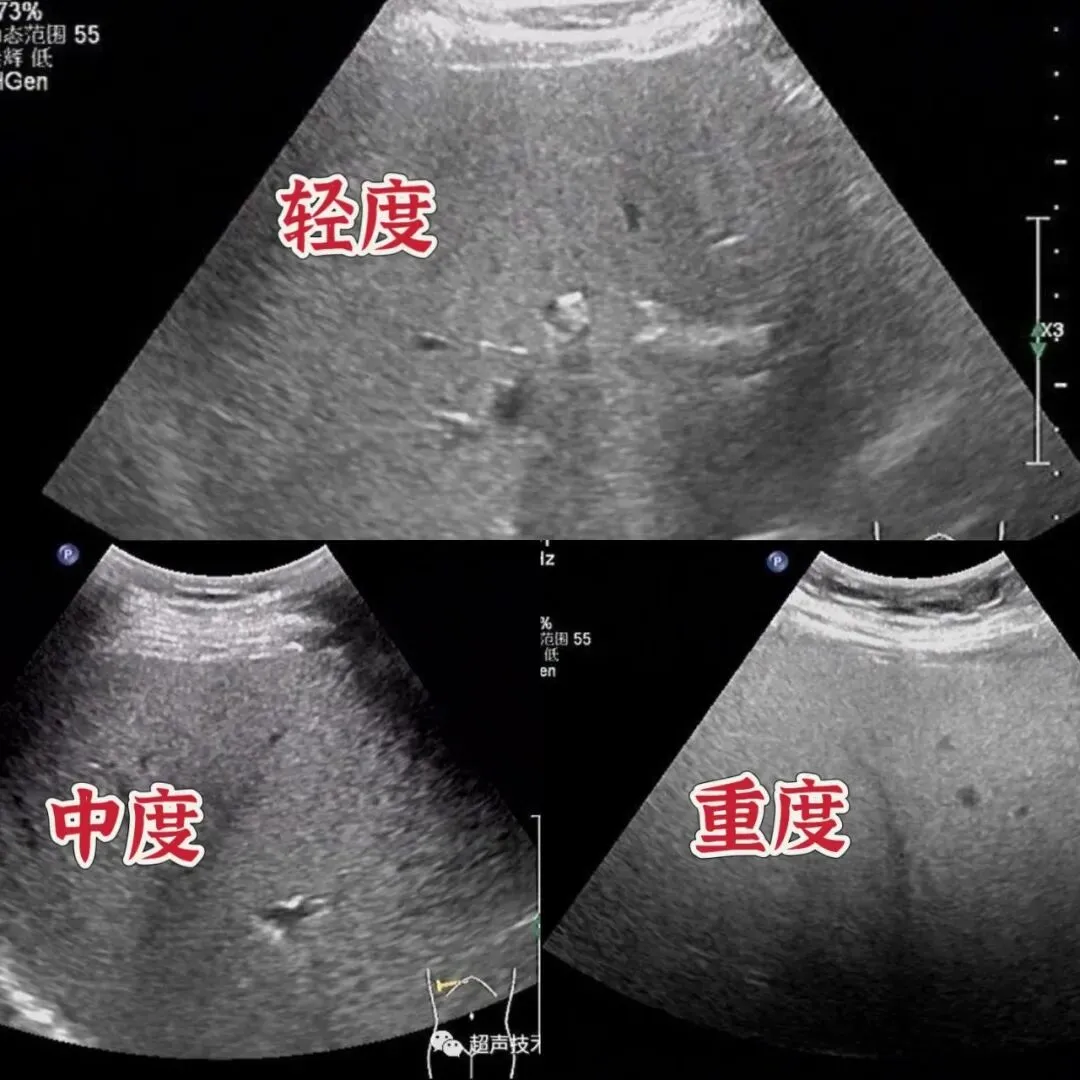

超声波(B超)是筛查脂肪肝的首选方法,专业的超声设备(如医技科使用的是迈瑞DC-33彩超)能够捕捉肝脏的微妙变化,仿佛为肝脏进行了一次“高清健康扫描”。其高分辨率成像技术与先进的图像处理算法,有效消除图像噪声,清晰展现组织细节,使不同级别的脂肪肝特征一目了然:

- 轻度:近场回声如被“薄雾”轻笼,远场衰减不明显,血管纹理清晰可见。

- 中度:肝脏体积略微增大,远场1/2区域出现回声衰减,血管轮廓仍可辨认。

- 重度:实质回声似“白雪皑皑”,远场2/3以上区域衰减,关键信息如膈肌与肝脏的边界依然清晰可辨,这些精准的影像资料是医生做出准确判断的关键,也是脂肪肝早期发现的重要保障。